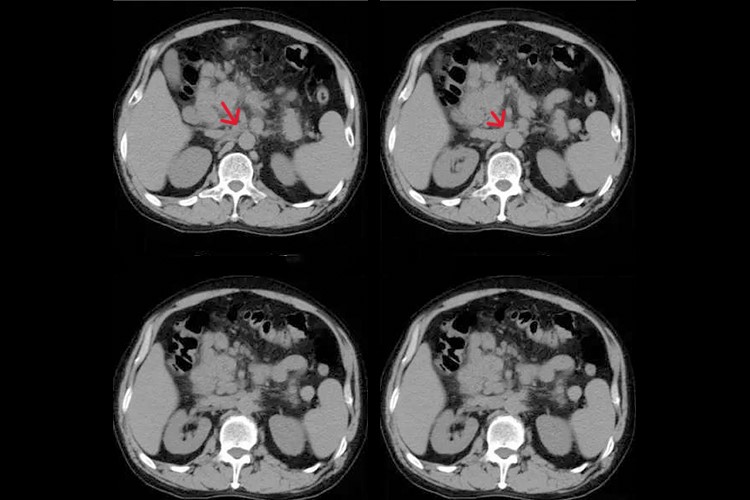

霍奇金淋巴瘤的主要症状为全身多处淋巴结增大,易累及腹膜后淋巴结,伴有发热、盗汗、瘙痒及消瘦等全身症状,常以原因不明的持续发热为起病症状。患者一般年龄稍大,男性较多,年轻女性自觉瘙痒可为霍奇金淋巴瘤的唯一全身症状。